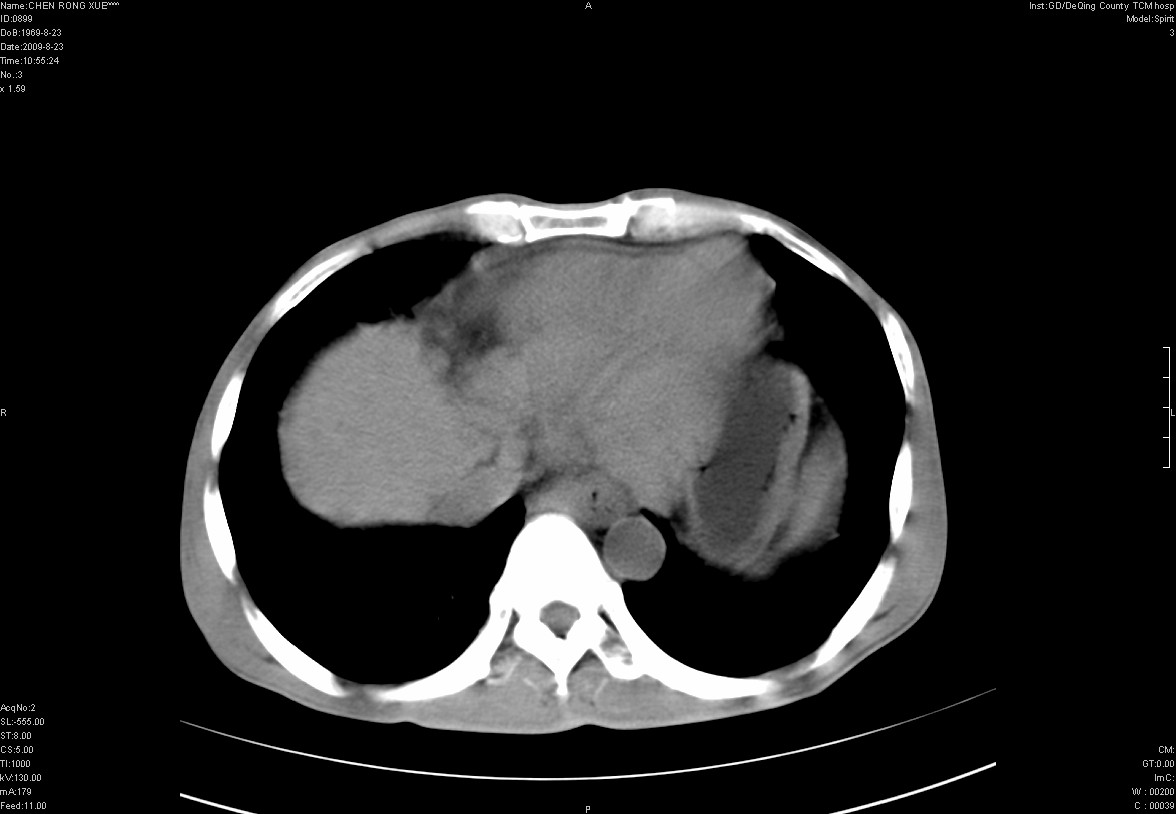

以下是引用zxl51642在2009-8-23 12:56:00的发言:[br]1、肝硬化、脾大;2、慢性胆囊炎;3、右肾占位并右侧腰大肌受侵,考虑恶性可能性大,建议增强扫描进一步检查。

以下是引用qiuleiyu在2009-8-23 15:17:00的发言:[br]1、慢性肝病,肝硬化,脾大,门脉高压。胆囊小结石。[br]2、右肾明显肿大,伴片状低密度灶,累及右侧腰大肌,肿瘤及炎症性病变皆有可能大,建议增强。

以下是引用zjzjr在2009-8-23 17:42:00的发言:[br]1、慢性肝病,肝硬化,脾大,门脉高压。胆囊小结石。[br]右肾脓肿波及肾周,建议增强